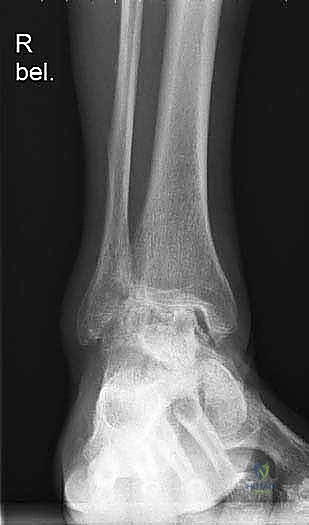

لفهم أهمية جراحة استبدال الكاحل، يجب أولاً فهم تشريح هذا المفصل المعقد. يتكون مفصل الكاحل من التقاء ثلاث عظام رئيسية:

1. عظمة الظنبوب (Tibia): وهي عظمة الساق الكبرى التي تشمل الجزء الداخلي والعلوي من الكاحل.

2. عظمة الشظية (Fibula): وهي عظمة الساق الصغرى التي تشكل الجزء الخارجي من الكاحل.

3. عظمة الكاحل (Talus): وهي العظمة السفلية التي ترتكز عليها عظام الساق وتعمل كمفصلة للحركة.

تُغطى نهايات هذه العظام بطبقة ناعمة ومرنة تسمى الغضروف المفصلي، والذي يعمل كوسادة لامتصاص الصدمات وتقليل الاحتكاك أثناء الحركة. عندما يتآكل هذا الغضروف، تبدأ العظام بالاحتكاك ببعضها البعض، مما يسبب ألماً مبرحاً وتورماً وتيبساً.

يتم إجراء فحوصات شاملة تشمل الأشعة السينية (X-rays)، والأشعة المقطعية (CT scan) لإنشاء نموذج ثلاثي الأبعاد لكاحل المريض. يساعد هذا د. هطيف في اختيار الحجم الدقيق للمفصل الصناعي وتحديد زوايا القطع بدقة متناهية.